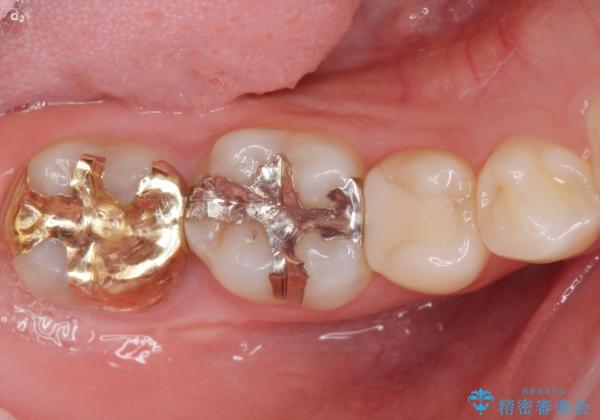

レントゲンで見つかった歯と歯の間の虫歯をセラミックインレーで修復

- 定期検診でレントゲンを撮ったら虫歯(カリエス)があったため、e-maxインレーにて治療しました。

治療した歯は過去に樹脂で治療されていて、虫歯が再発していました。

樹脂の治療は経年的に劣化し、また歯質との隙間ができて虫歯の再発リスクが高いです。

e-max(セラミック)の治療は劣化をせず、歯質との隙間もできないため虫歯の再発のリスクが低いです。